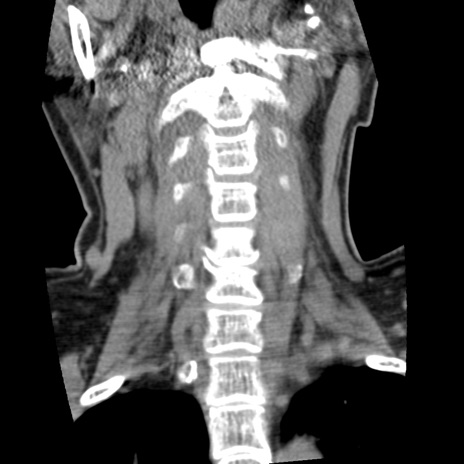

症例50 頚椎CT(冠状断像)

【症例】60歳代女性

【主訴】後頭部〜右後頸部にかけての痛み

【現病歴】本日飲食店でコーヒーを飲んでいたところ、突然後頭部〜右後頸部にかけて痛みが出現し、右上肢の感覚障害を伴ったため救急要請。

【身体所見】脳神経学的に明らかな異常所見を認めず。右上肢に軽度の感覚障害あり。

異常所見と診断は?

頚椎CT